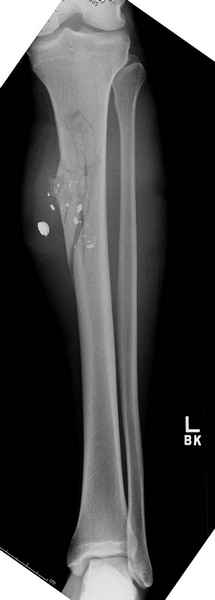

2 перелом бедра

Имя     : 1 GSW.jpg

Тип     : image/jpeg

Размер  : 16781 байтов

Описание: отсутствует

Url     : http://weborto.net:8080/pipermail/ortho/attachments/20090726/b21ae3ea/attachment-0015.jpg